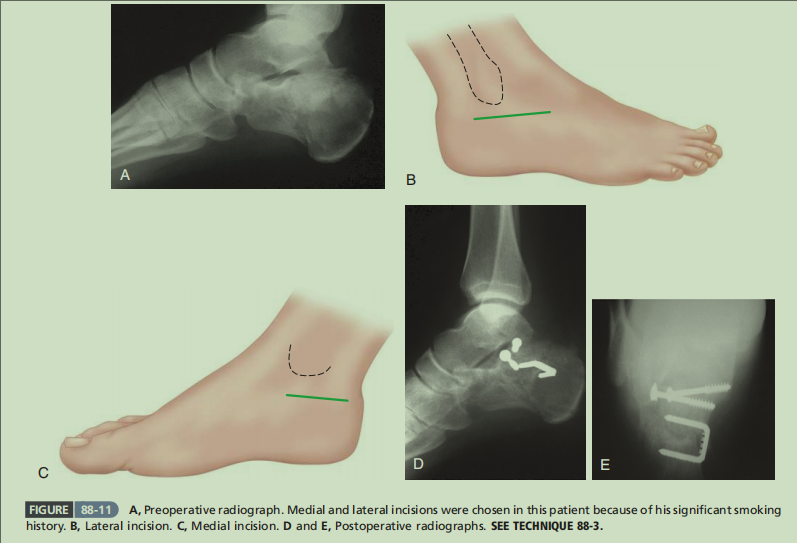

还是首先介绍了大L切口,图D展示了后足内翻的纠正方法。

术后轴位片显示了后足内翻的纠正,载距突螺钉的方向和长度值得学习。但图B选择克氏针穿过距骨来进行临时固定是否恰当,这个由各位同仁自己评判。